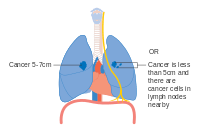

Lung cancer staging is an assessment of the degree of spread of the cancer from its original source.[71] It is one of the factors affecting the prognosis and potential treatment of lung cancer.[6][71]

The evaluation of non-small-cell lung carcinoma (NSCLC) staging uses the TNM classification. This is based on the size of the primary tumor, lymph node involvement, and distant metastasis.[6]

Using the TNM descriptors, a group is assigned, ranging from occult cancer, through stages 0, IA (one-A), IB, IIA, IIB, IIIA, IIIB and IV (four). This stage group assists with the choice of treatment and estimation of prognosis.[73]

- Diagrams of main features of staging

Stage IA and IB lung cancer

Stage IIA lung cancer

Stage IIB lung cancer

One option for stage IIB lung cancer, with T2b; but if tumor is within 2 cm of the carina, this is stage 3